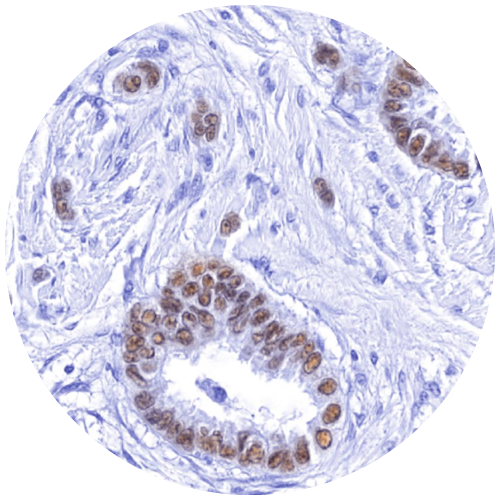

ViewsML uses virtual biomarker staining

in AI-driven diagnostics, discovering deeper

cell-level insights for better patient outcomes

Advantages of Virtual Staining

Multiplexing allows for greater biomarker characterization

Consistent and reproducible immunostaining, every time

May be trained to any biomarker across any disease type and species